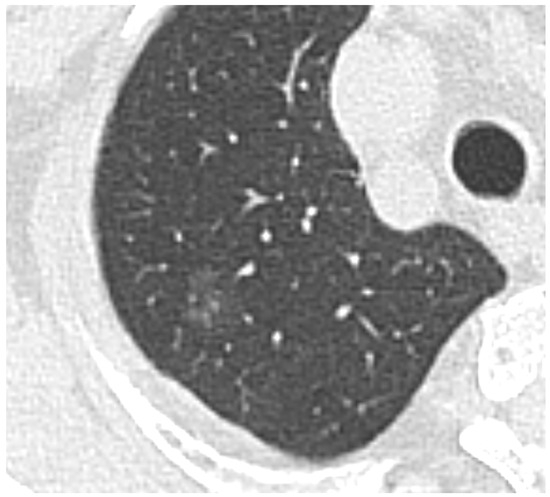

- Developments in low-dose CT screening;

- low-dose CT screening

- medical imaging

- lung nodules